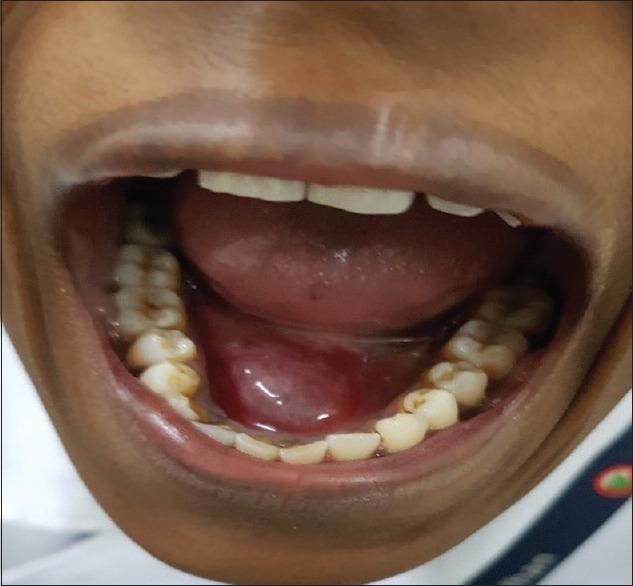

Progesterone-induced Angina Bullosa Hemorrhagica.

Indian J Dermatol. 2021 Jan-Feb;66(1):103-105. doi: 10.4103/ijd.IJD_274_19.

Progesterone-induced Angina Bullosa Hemorrhagica.孕激素诱导的出血性大疱性心绞痛。